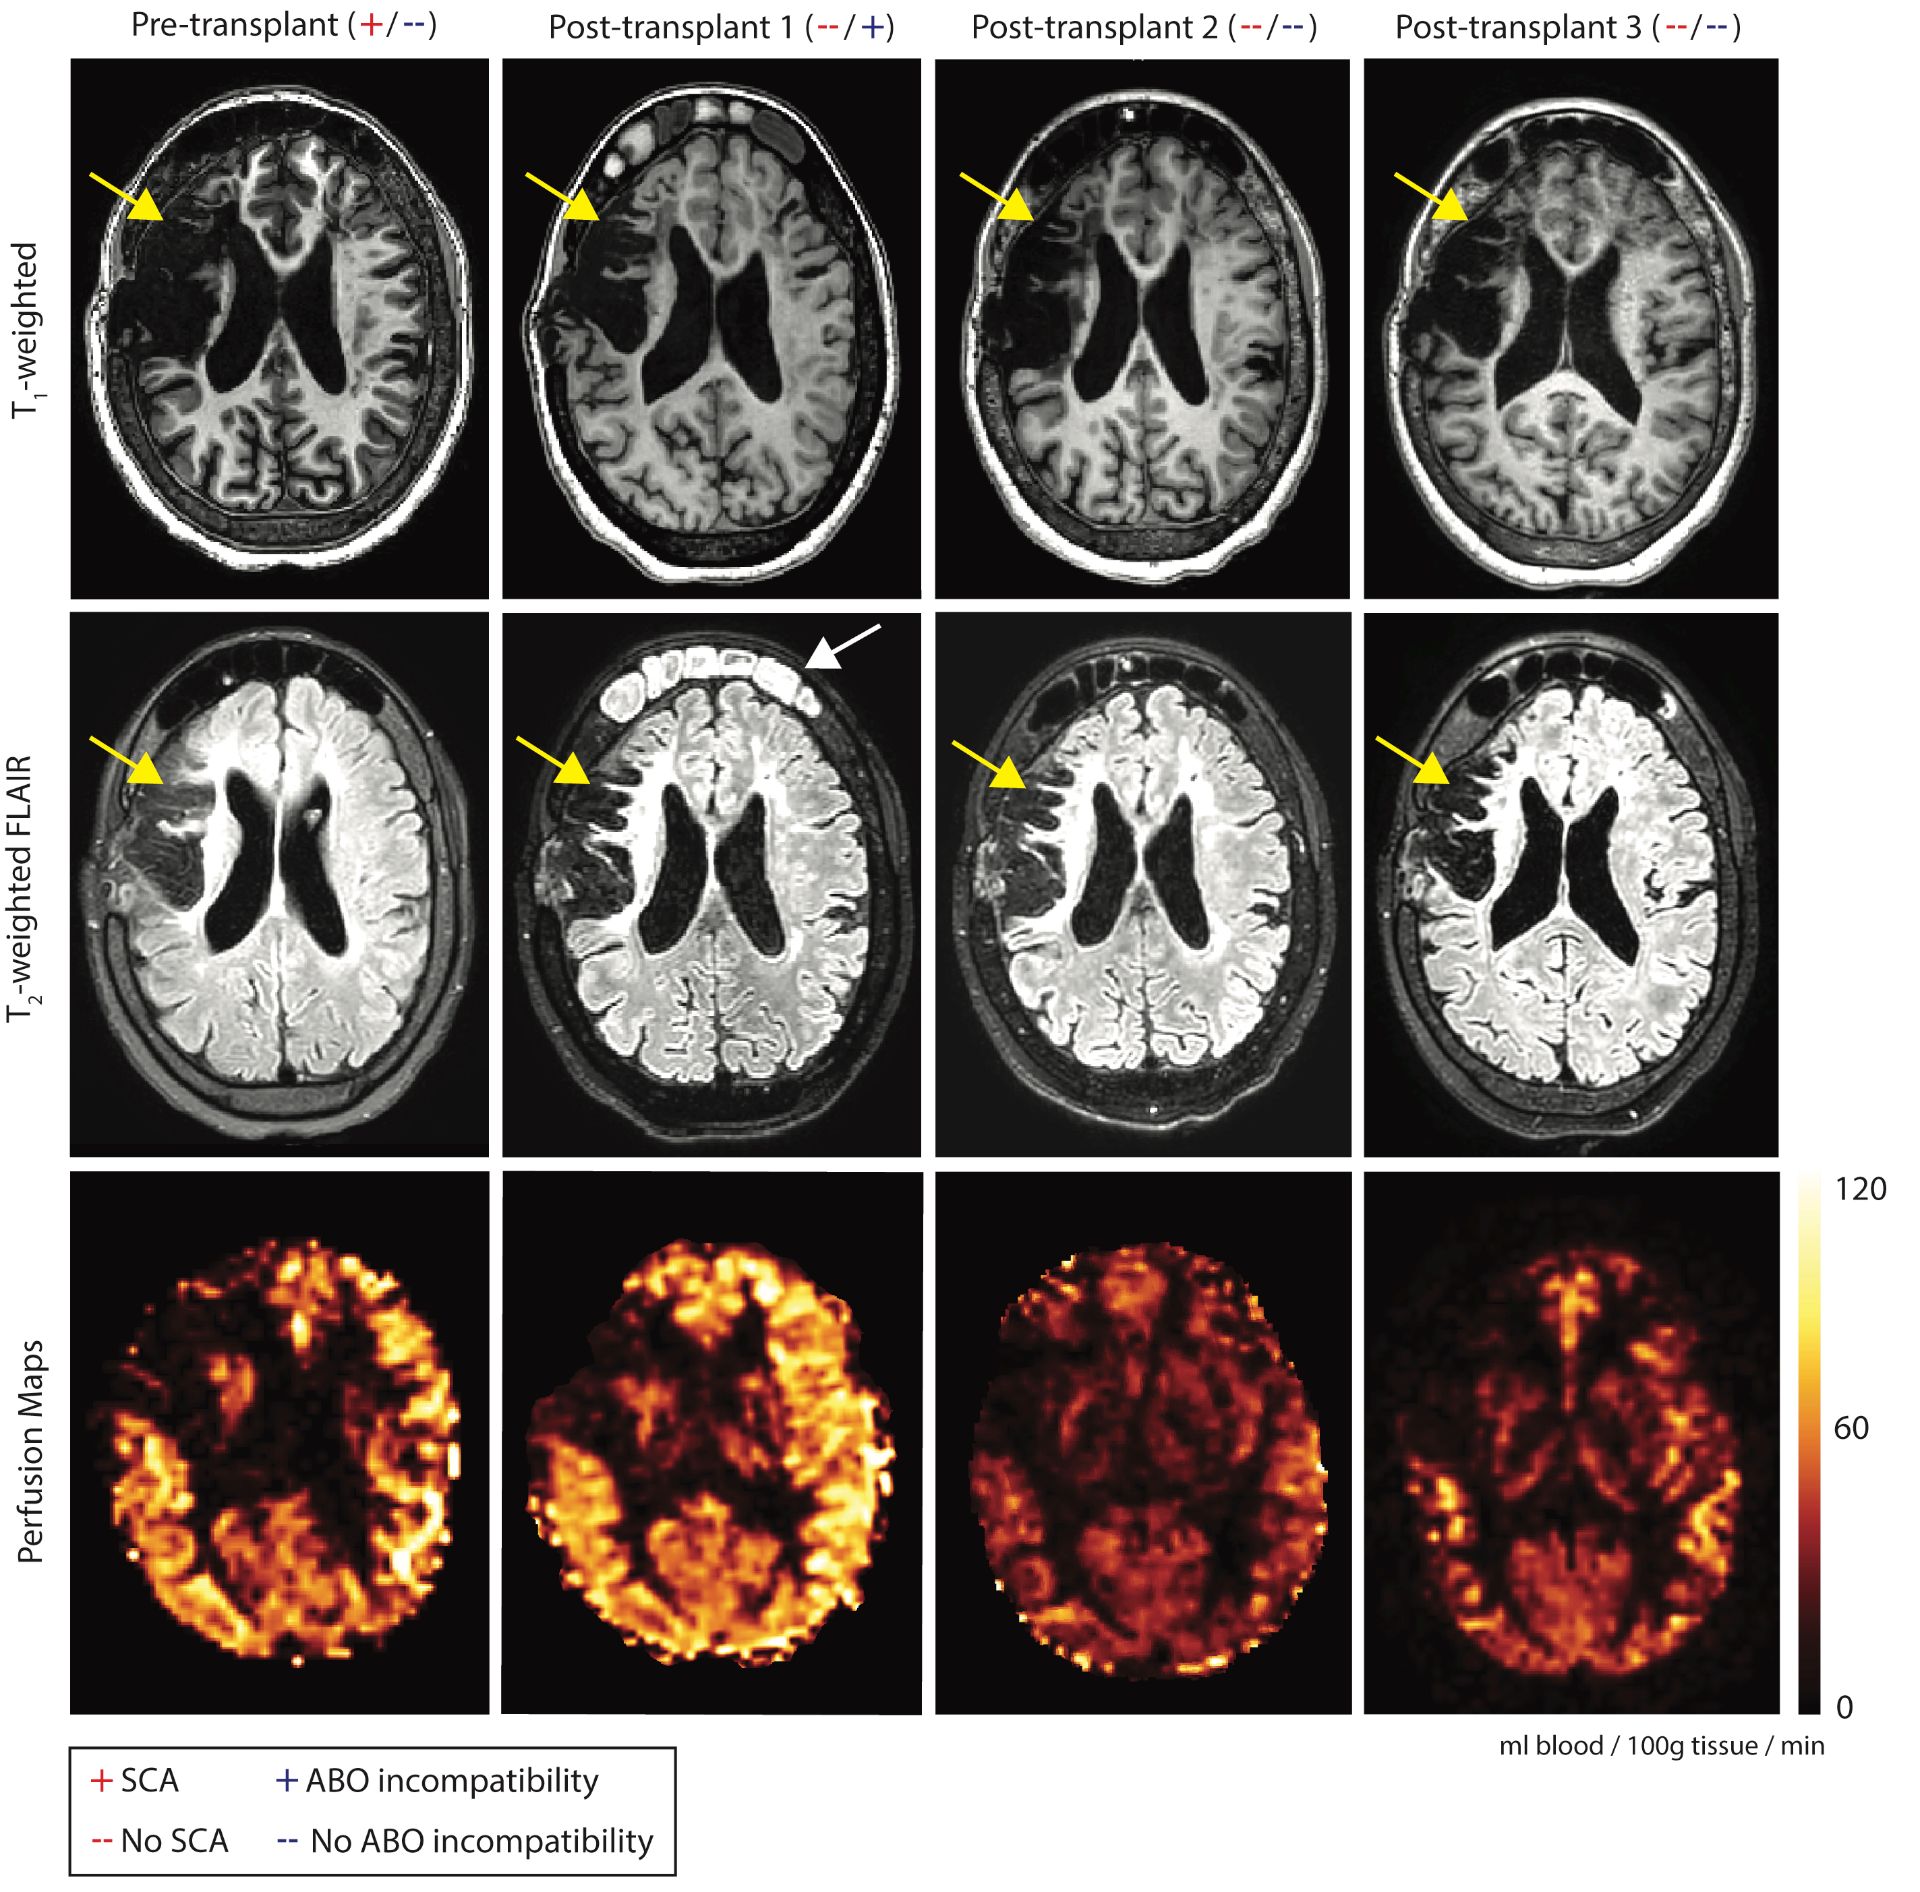

In her 20s, HSCT was recommended as curative treatment and was approved on an institutional transplant protocol due to stroke and MMS progression risk, and transfusion iron overload despite chelation. A non-myeloablative haploidentical bone marrow transplant (haplo-BMT) was prescribed, as the patient had no matched sibling and poor unrelated donor options. Her brother was identified as a haplo-match and served as the donor, with phenotype HbAA ABO blood type B+, while the patient was O+. Prior to HSCT, the patient underwent a MRI of the brain, including pseudocontinuous arterial spin labeling (pCASL) perfusion9 and oxygen extraction fraction (OEF)10 imaging. Pre-transplant, chronic left and right frontoparietal infarcts were noted, along with large areas of encephalomalacia in the middle cerebral artery distribution bilaterally. MR angiography was unchanged from prior studies. The patient’s hematocrit was 30%, with a moderately-elevated cortical CBF of 66.2 ml/100g/min in non-infarcted tissue and approximately normal OEF of 31.8%.

While engraftment was successful (HbAA genotype, 100% donor), the patient developed pure red cell aplasia (PRCA) related to the ABO incompatible HSCT, an autoimmune issue resulting in transfusion-dependent anemia. At this first post-transplant timepoint, the patient’s hematocrit was maintained at 25% with transfusion support. The patient’s CBF rose to 75.8 ml/100g/min with persistent anemia, and her OEF increased to 39.3%. No new infarcts were noted at this time, but cerebral hemodynamic measures remained concerning.

To address her PRCA and need for ongoing blood transfusions, the patient received two rituximab infusions, which were ineffective. She was subsequently given weekly injections of daratumumab 1800 mg for four weeks, which successfully treated her PRCA.11 Her hematocrit rose to 39%, within a normal range [36-48% in women],12 and has been maintained without transfusions. Correspondingly, CBF largely normalized to 38.2 ml/100g/min [normal range = 40-65 ml/100g/min],13,14,15 and the patient’s OEF was assessed at 36.3% [normal range = 35-45%].16 At a fourth timepoint, approximately three years post-transplant, cerebral hemodynamic measures remained stable, with hematocrit=41%, CBF=46.3 ml/100g/min, and OEF=40.4%. Overall, from pre-HSCT to post-HSCT after treatment for ABO incompatibility, the patient’s hematocrit increased, CBF normalized to an approximately healthy value (Figure 2), and OEF adjusted slightly, albeit within a normal range. No new strokes or silent cerebral infarcts have developed, and her cerebral vasculopathy remains severe but is stable at three years post-transplant (Figure 3).

Figure 2. Anatomical imaging of our patient with sickle cell anemia (HbSS) and moyamoya syndrome vasculopathy who was in her 20s at the time of imaging. Magnetic resonance images show chronic infarction (yellow arrows) throughout the right hemisphere on axial T1-weighted and T2-weighted FLAIR images at pre-transplant, post-transplant with ABO incompatibility (post-transplant 1) and post-transplant after successful treatment for pure red cell aplasia (post-transplant 2 and 3). At post-transplant 1, as an incidental finding, opacification of the frontal sinuses and mucosal thickening of the maxillary sinus is visible (white arrow). Bottom row: Perfusion maps show pre-transplant cerebral blood flow (CBF=66.2 ml/100g/min) is elevated secondary to anemia with hemoglobin level of 10.4 g/dL and increases at post-transplant 1 during ABO incompatibility (CBF=75.8 ml/100g/min, Hb=8.1 g/dL). However, CBF reduces to an approximately normal range outside of the infarct region at post-transplant 2 (CBF=38.2 ml/100g/min), with increased hemoglobin level of 13.3 g/dL, consistent with improved oxygen carrying capacity post-engraftment. At post-transplant 3, CBF remains stable within healthy physiological range (CBF=46.3 ml/100g/min), with a stable hemoglobin of 13.6 g/dL. See color bar on the right side of the figure, which shows CBF in ml/100g of brain tissue/minute.